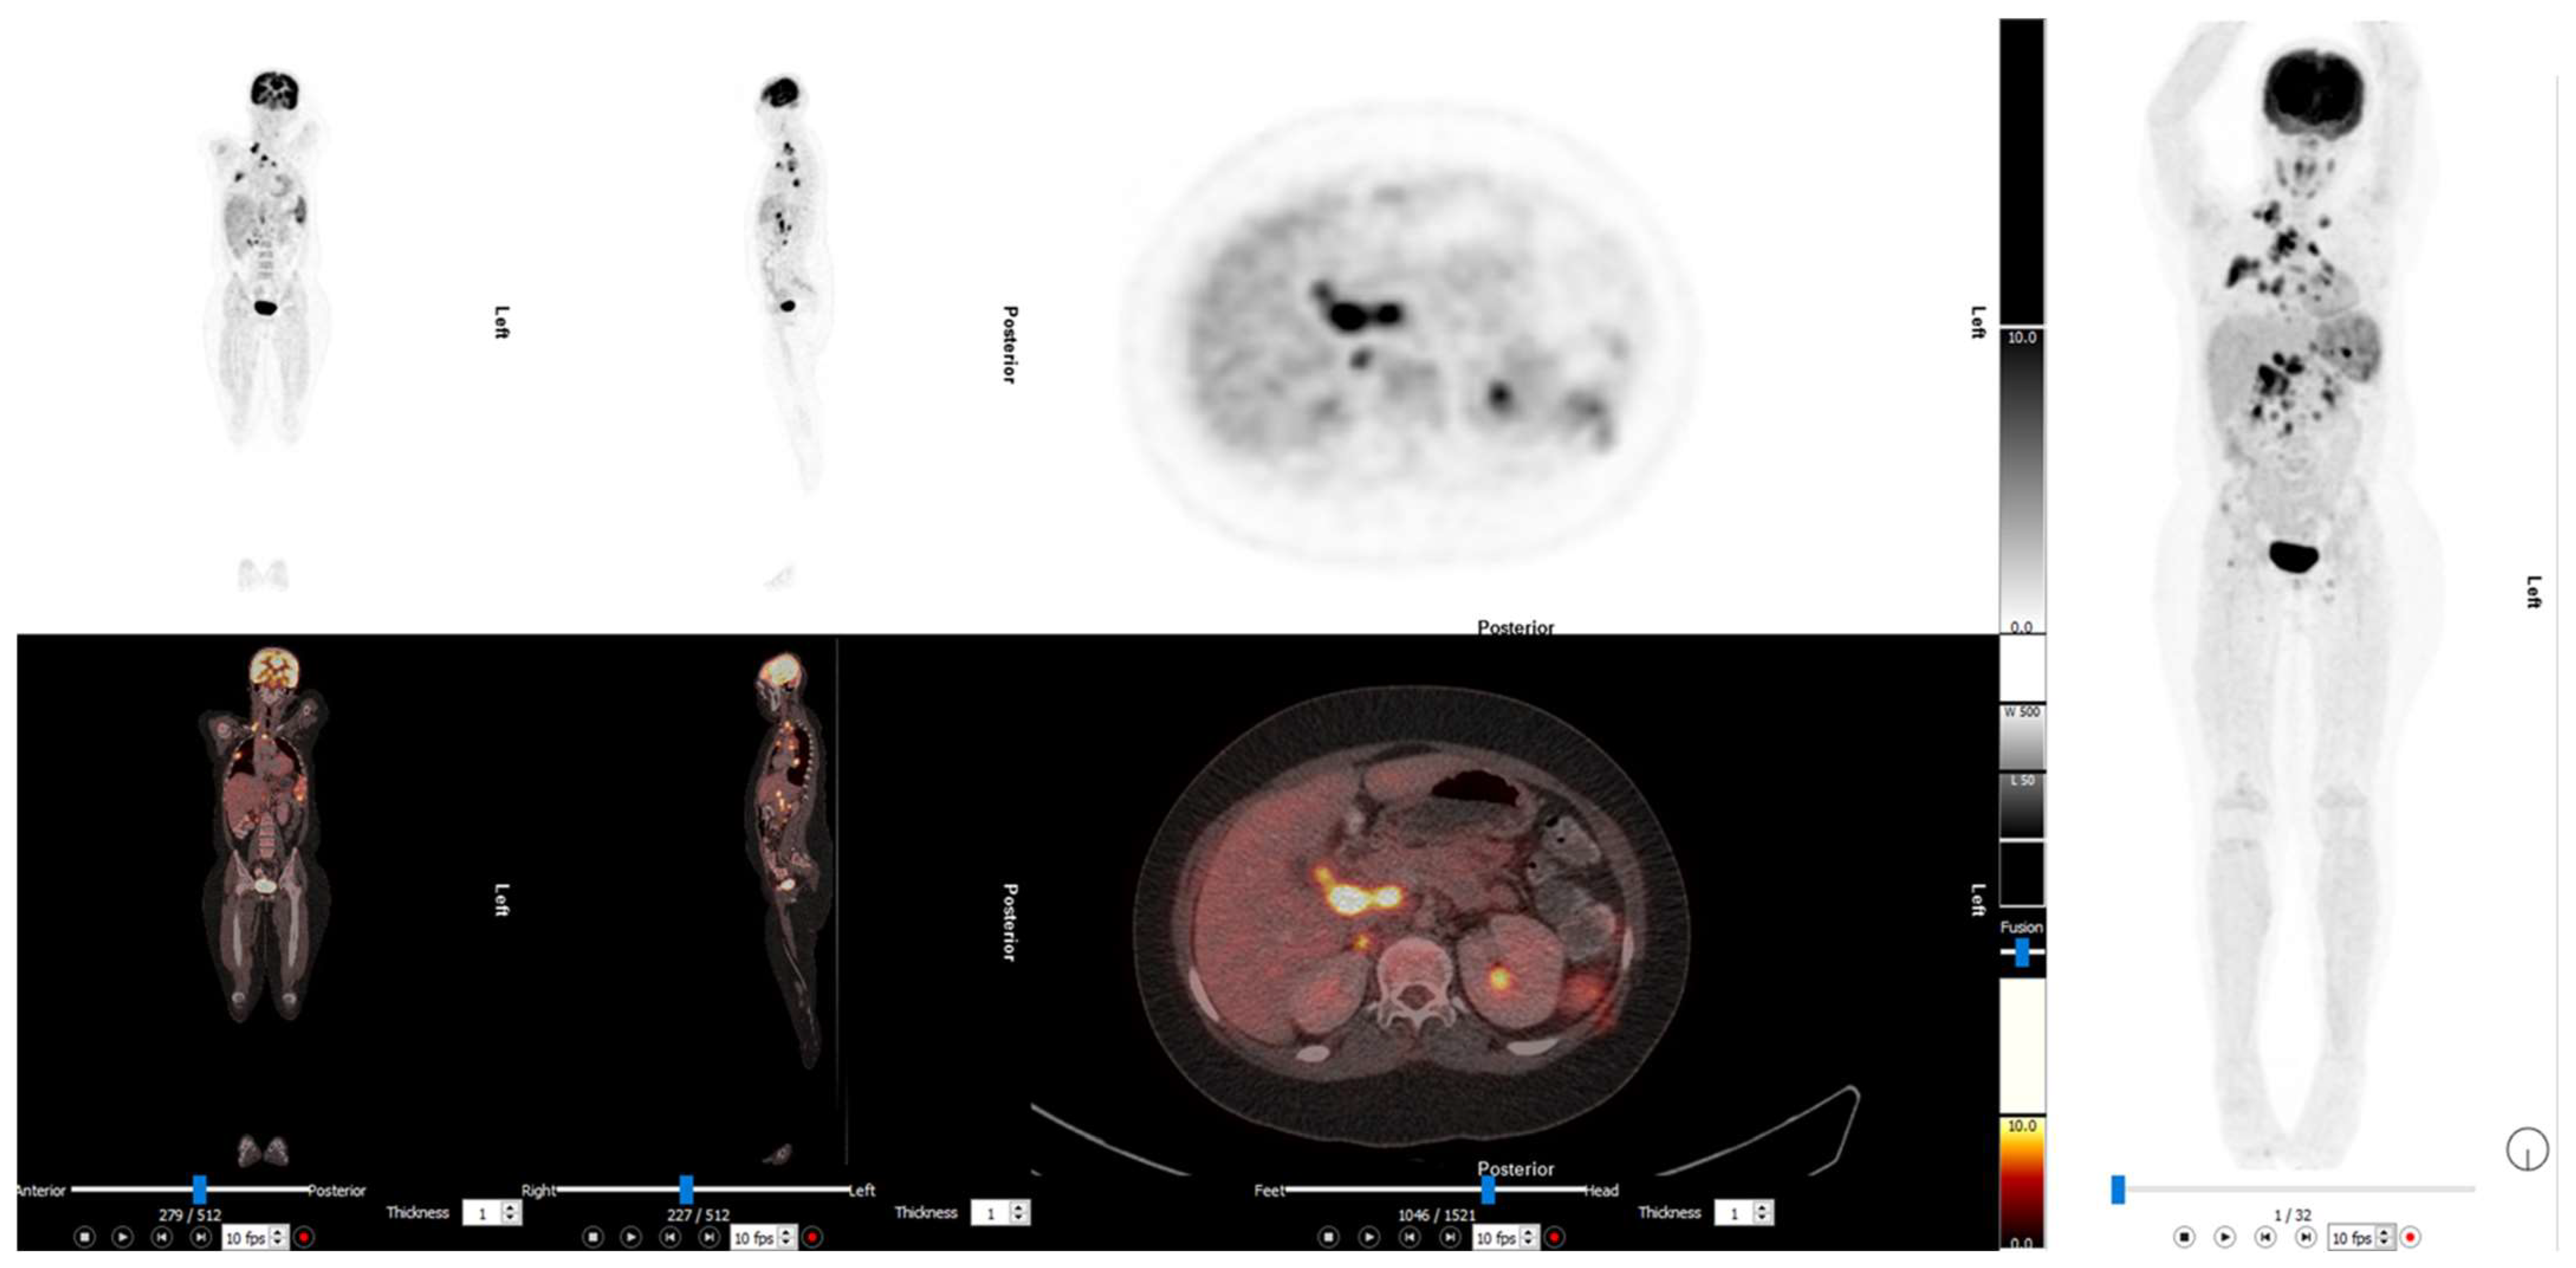

2. Paediatric Lymphoma

3. Neuroblastoma

3.1. 2-[18F]FDG PET/CT in Neuroblastoma

3.2. [124I]mIBG PET/CT in Neuroblastoma

3.3. [68Ga]DOTA-SSA PET/CT in Neuroblastoma

3.4. [18F]F-DOPA PET/CT in Neuroblastoma